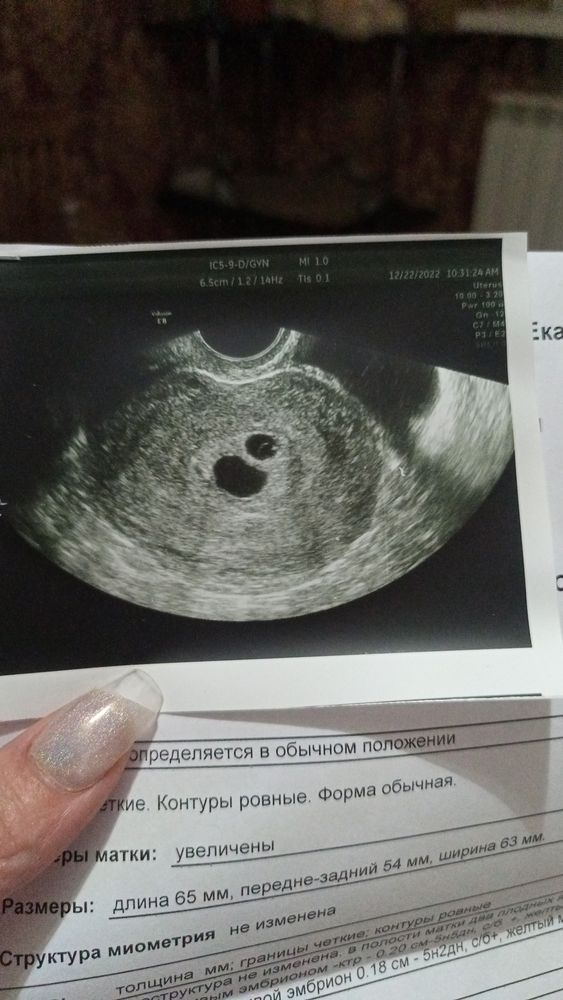

Девочки, кто разбирается ? Переживаю , что 2 🪺 на много меньше . 😭 .Перенесли 1❄️

Надя , перенесли 1 5-дневку . Естественная беременность не может быть из-за отсутствия труб. И у меня два плодных яйца

У меня тоже была разница на первом узи - 4 мм , вот через недельку она и осталась , только когда звучит 10 и 6 это большая разница вроде , а когда 21 и 25- то и мелочь 😀